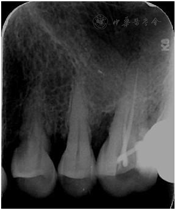

2016年6月1日后复查:口腔卫生状况一般,菌斑、软垢少量,龈下牙石(+-++)。牙龈色稍红,肿胀,形态稍圆钝,质软,出血指数3~。全口牙齿探诊深度(PD)4~6 mm,个别位点7~8 mm,较前略有改善。龈退缩2~3 mm,32~42Ⅰ~Ⅱo松动。48牙冠周围软垢较多,颊侧附着龈缺如(图6,图7,图8,图9,图10)。26远中龋坏,探诊敏感,冷热测激发痛,叩痛(-)。

全口影像学检查:12~22、25~26、34~36、45~46牙槽骨吸收进一步加重,但下颌出现骨白线,26远中冠部低密度影像近髓腔,根尖周无低密度影像。